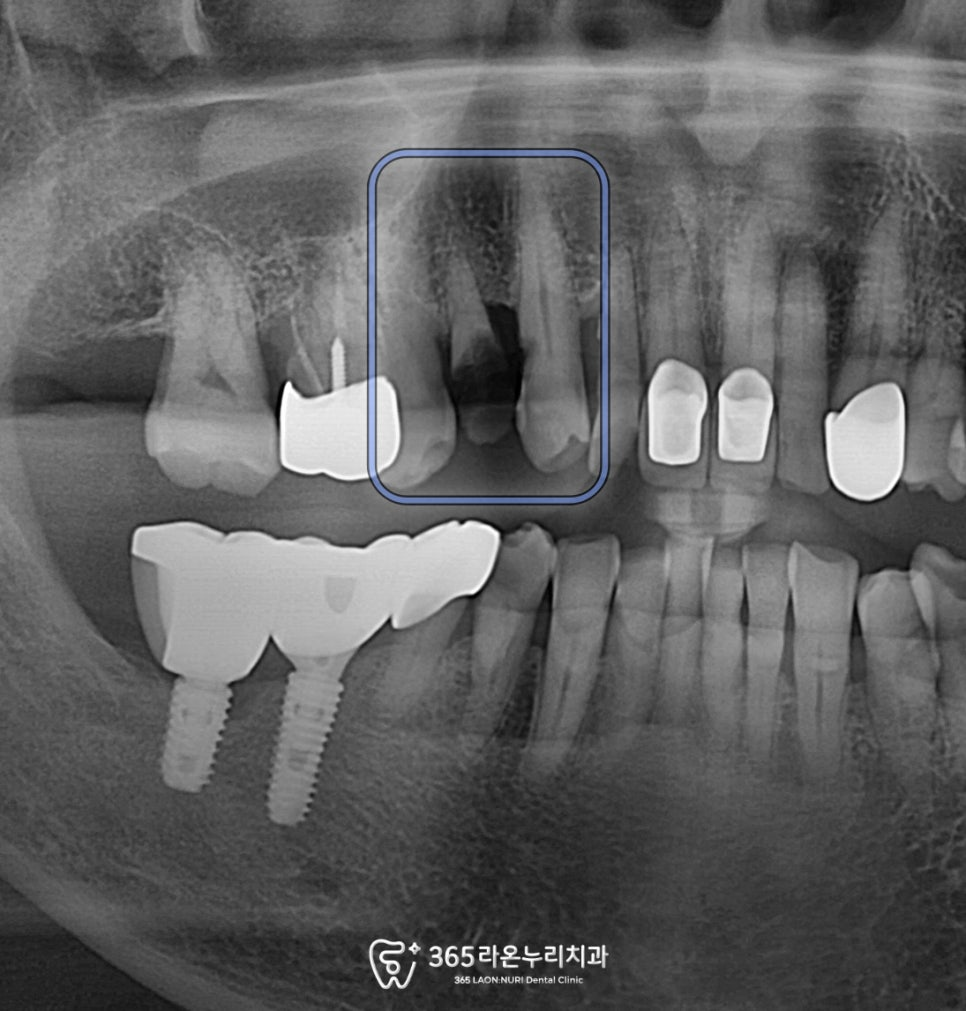

우선 구강 상태를 정확히 파악하기 위해

남촌동 치과 에서

파노라마 사진부터 보겠습니다.

2025.1.2

치관이 아예 부러져 치근만 남아있었는데요.

파노라마 상으로 치근단 병소가 확인되는 걸 보아

치근 우식이 심하게 진행된 것으로 진단되었습니다.